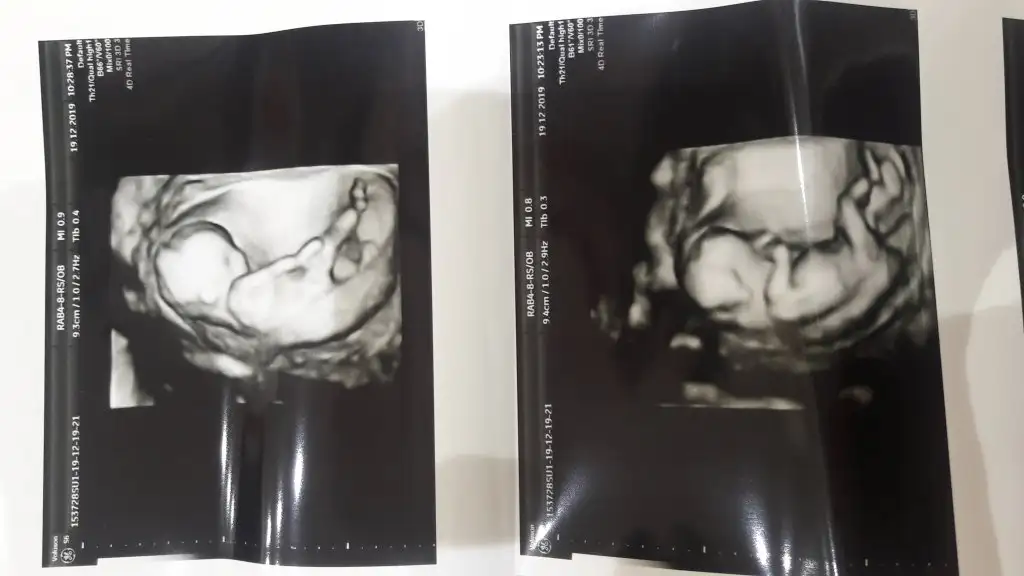

ay yarn söylm bakimmmEvet canim normal ultrasonuyla vakti iyi cok sukur dedi.1,5 cikti ense kalinligi.3 ve ustu olursa endise ederiz dedi.

Bende yaptirdim ama tek basina ultrosan yeterli degilmi acaba sonuc degerlendirmek icin ultrosanda hersey guzel bizimde 1mm. dra.sormayi unuttum haftaya cikacakBizimde 1mm kızlar ense kalınlığımız ama 2li testi yaptırın bence mutlaka

Ben dün yaptırdım kan verdim 3 haftaya çıkar dediler ense ve burun için baktı usg den ve iyi dedi binlerce kez şükürler olsun herkes bu sözleri duysun insallah gittiğindeBende yaptirdim ama tek basina ultrosan yeterli degilmi acaba sonuc degerlendirmek icin ultrosanda hersey guzel bizimde 1mm. dra.sormayi unuttum haftaya cikacak

Ense kalınlığı sonuçlarda NT olarak (Nuchal Translucency) yazıyor canım, çıkınca bakabilirsin karşılığına.Ben dün yaptırdım kan verdim 3 haftaya çıkar dediler ense ve burun için baktı usg den ve iyi dedi binlerce kez şükürler olsun herkes bu sözleri duysun insallah gittiğindeense kaç cm hiç sormadım ben ya kağıtlarda yazar mi ki ne diye yaziyo